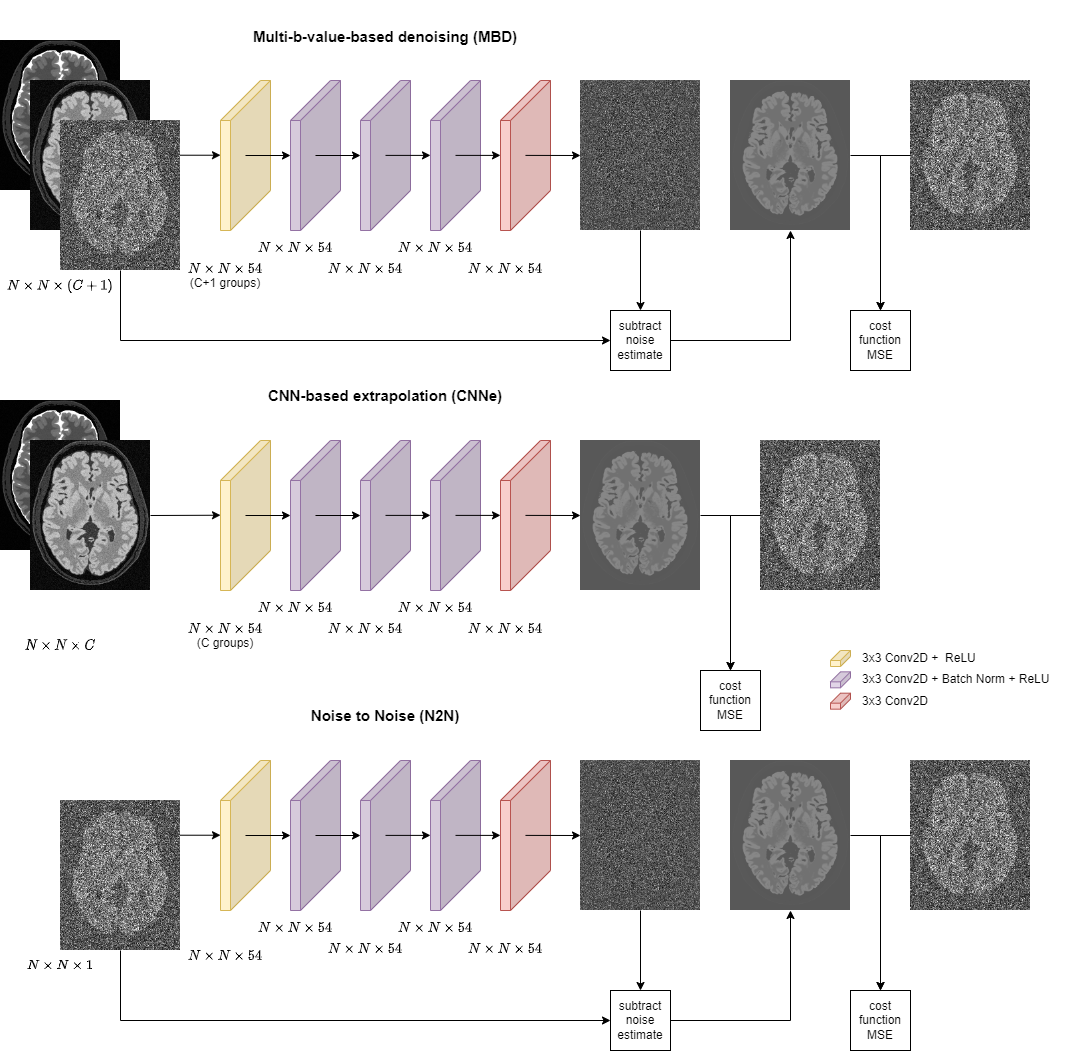

This shows that noisy images can be used as targets to train a denoiser and is the basis for Noise2Noise [11]. For images corrupted with zero-mean Gaussian noise, such as complex-valued MRI, one can expect no bias from N2N denoising. For Rician noise, however, N2N will reduce noise variance, but will keep the Rician bias since it is the expected intensity value of a voxel. A neural network architecture using N2N is shown in the bottom row in Figure 1. Typically, as an individual training vector, the network is fed with a single image, and a repeated measurement of that image, featuring independent noise, is set as the learning target.

In MBD, we modify the input to the N2N network [19] and supply a sequence of b-values as individual input channels to provide more information about the structure and diffusional properties of the tissues (top row in Figure 1). There is no theoretical limit on the number of the input channels, however, we currently investigated cases that feature at most three b-values, corresponding to the practice of one of our partner hospitals. For example, denoising of b4000 images is learned based on pairs involving b0, b1000 and b4000 images as input and the second repetition of b4000 images as targets. The choice of optimal b-values was not investigated in this paper (see Discussion), but we demonstrate using different datasets that the proposed method performed better than the reference methods regardless of the b-values involved.

For a better comparison with MBD, we propose a CNN-based extrapolation method (CNNe), similar in form to N2N and MBD. Referring to Eq. 4, CNNe is fed with image at b1subscript𝑏1b_{1}italic_b start_POSTSUBSCRIPT 1 end_POSTSUBSCRIPT and b2subscript𝑏2b_{2}italic_b start_POSTSUBSCRIPT 2 end_POSTSUBSCRIPT, while the training target is an image at some other b>b1,b2𝑏subscript𝑏1subscript𝑏2b>b_{1},b_{2}italic_b > italic_b start_POSTSUBSCRIPT 1 end_POSTSUBSCRIPT , italic_b start_POSTSUBSCRIPT 2 end_POSTSUBSCRIPT . This is shown in the middle row in Figure 1. In this setting, the network is forced to ’extrapolate’. In contrast to algebraic extrapolation, CNNe is expected to have denoising properties because the target image inherently features independent noise.

For all neural networks in this paper, we relied on the DnCNN architecture [23]. DnCNN features an input 2D convolutional layer with ReLU activation and an output linear convolutional layer. Between the input and output layers, there is a user-defined number of blocks, consisting of a convolution layer, batch normalization and ReLU. In our implementation, we used three such blocks, so the total depth is five layers. All layers compute 54 features except for the final. The first layer computes features in equally-sized groups, separately for each input channel, but keeping 54 features in total. Convolutions use 3×3333\times 33 × 3 kernels. The input is multichannel, with a different number of channels for N2N, MBD and CNNe. Originally, DnCNN estimates the noise instance and subtracts it from the input. This approach was used for MBD and N2N. For MBD, noise is estimated for the image at the desired b-value and subtracted from the corresponding input channel. CNNe directly estimates the noiseless image at the desired b-value.

Refer to caption

(a)

Figure 1: Configuration and architecture of the MBD, CNNe and N2N convolutional neural networks. Note the differences in the input, while the architecture and target data are the same. C𝐶Citalic_C is the number of input images (channels) for CNNe. C=2𝐶2C=2italic_C = 2 case is presented.